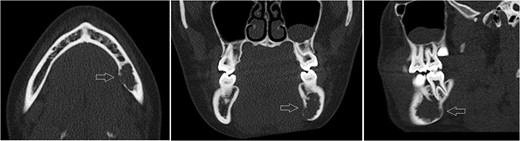

Axial, sagittal and coronar CT showing a 2 × 1 x 1.8-cm lesion in the left posterior mandible, its expansive and destructive character, and its penetration of the medial corticalis.